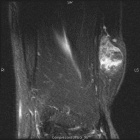

68 year old female with painless mass in right forearm

Zoom image: Radiological image Radiological image.